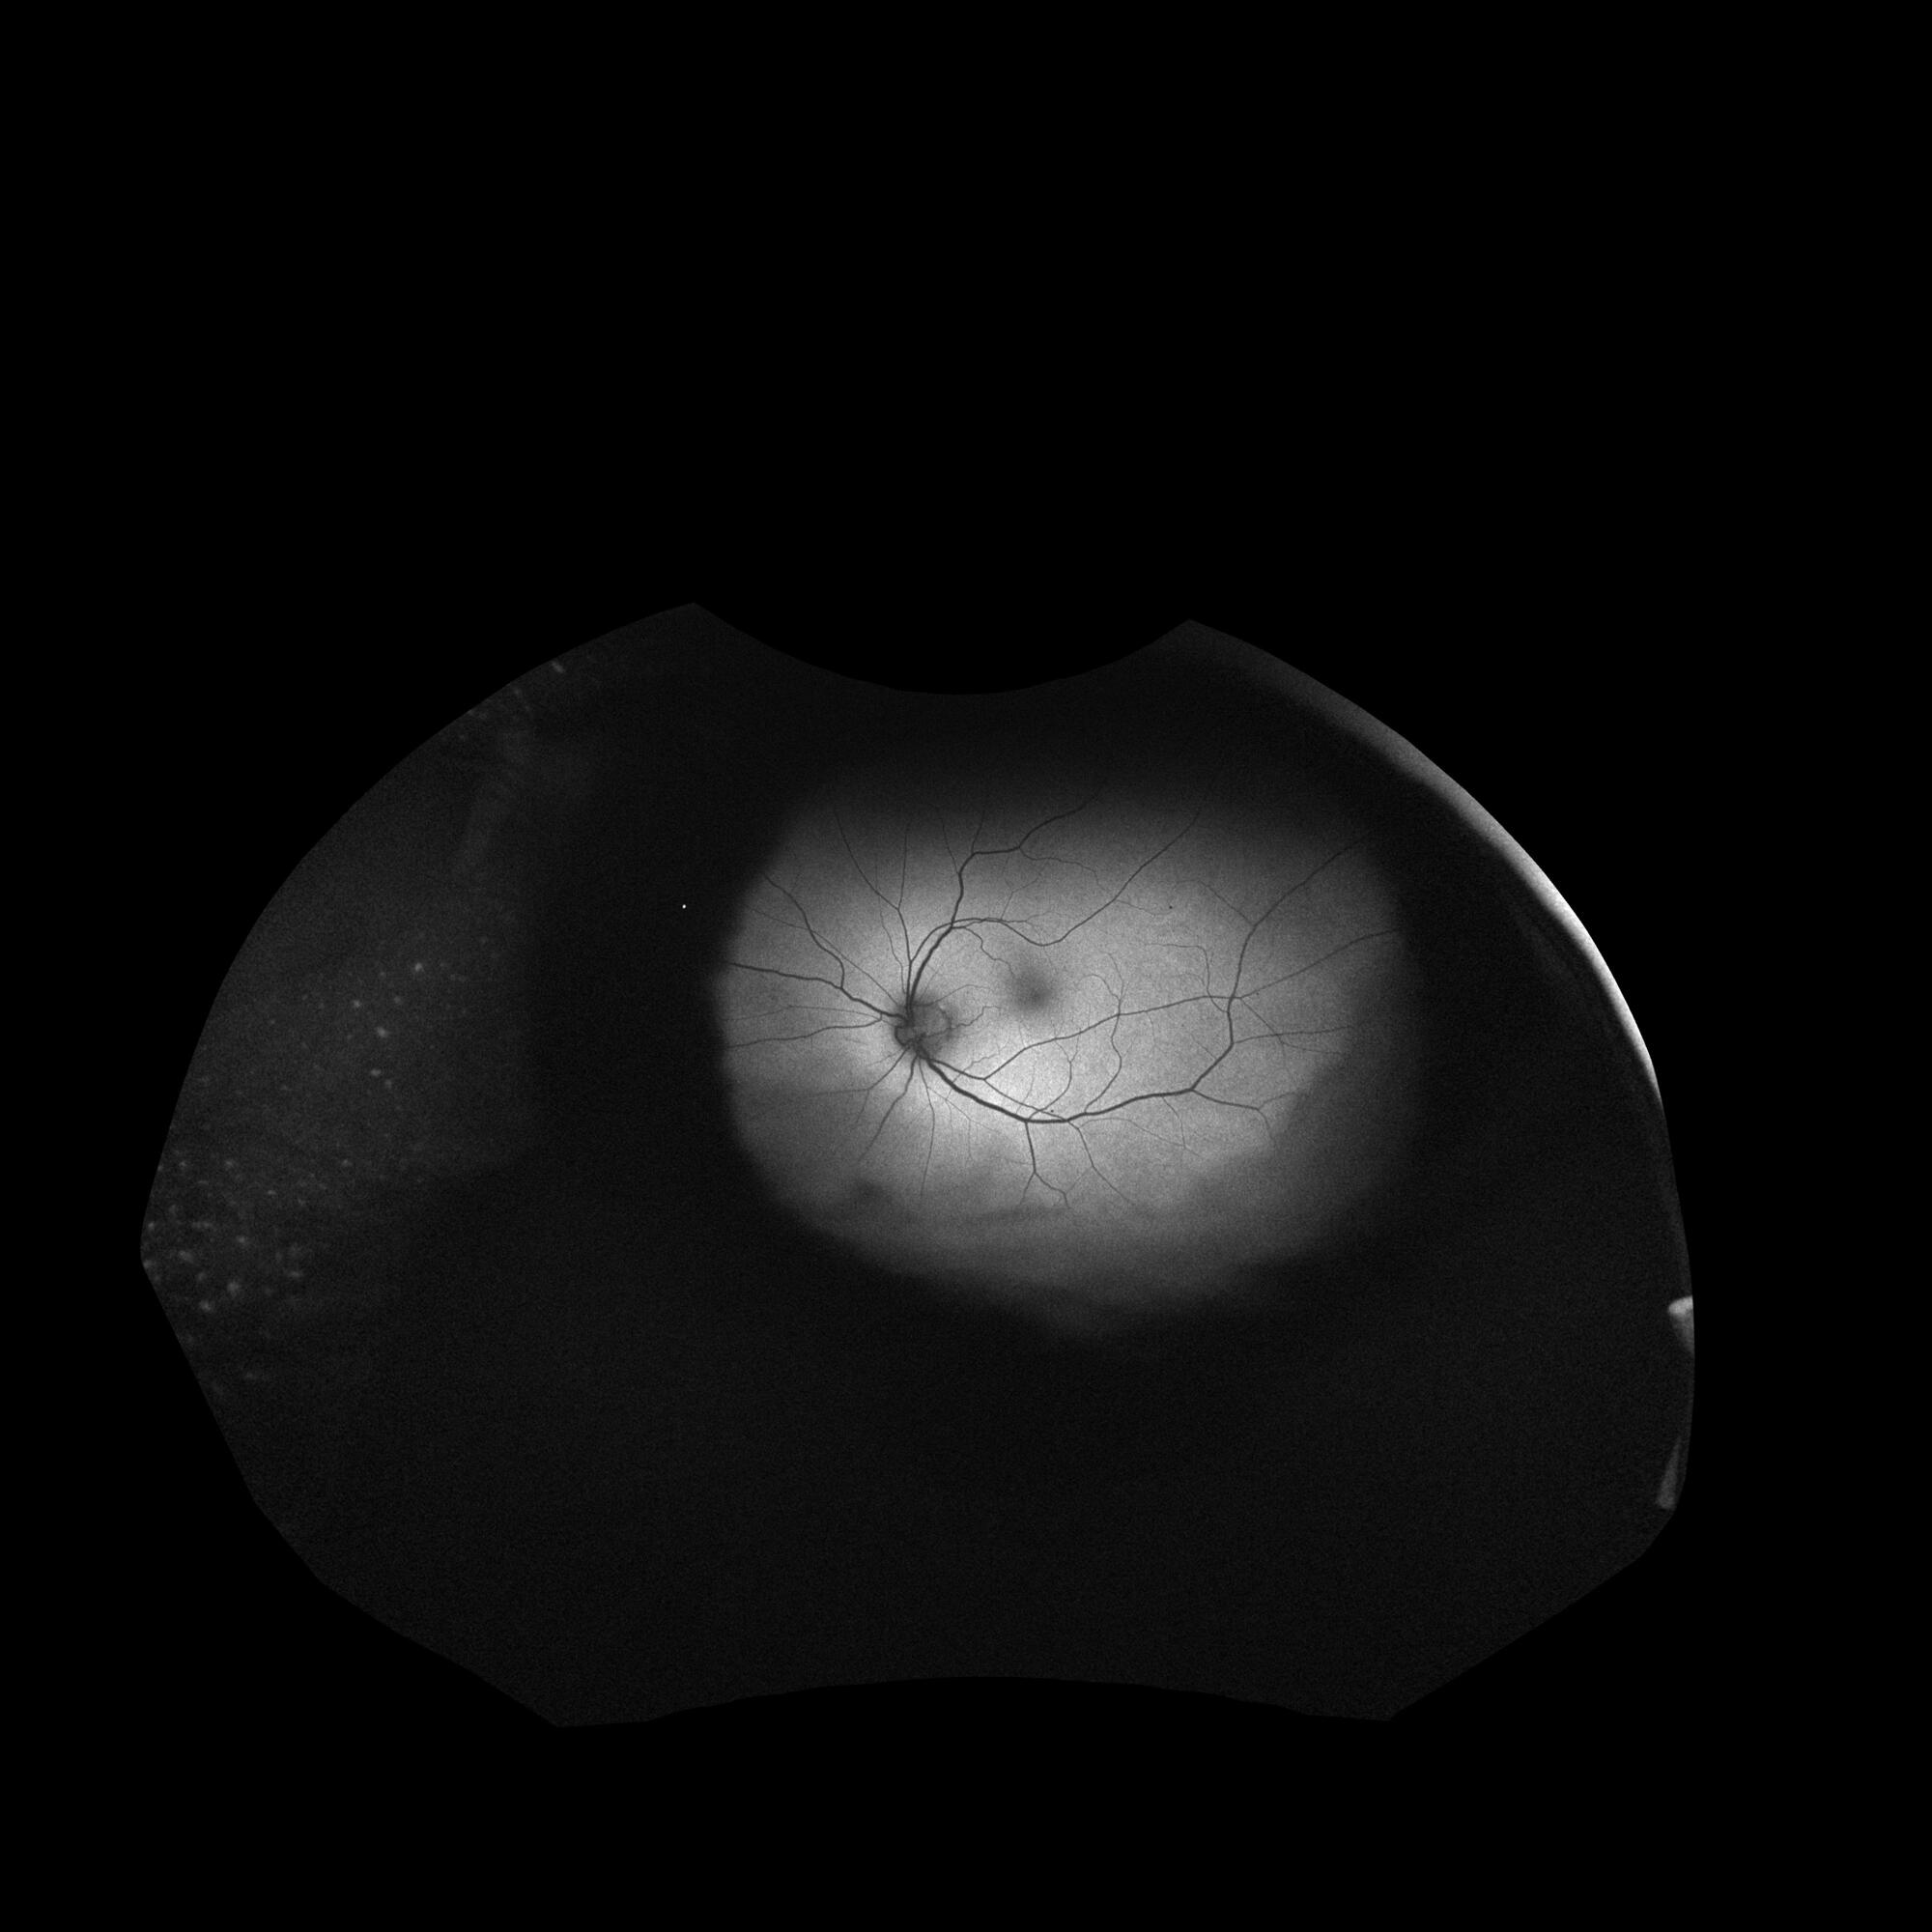

Figure 2: Examples of the synthetic images with the highest correlation to any real image. Pairs of synthetic images and the corresponding real image that it most closely resembles are displayed together with scatter plot of the pixel values and the correlation value. (a) OCTA-SMAC; (b) OCT-BONH; (c) OCT-BMAC; (d) FAF. For OCT-BMAC and OCT-BONH the synthetic images strongly resembled the real images but were not exact copies. For OCTA-SMAC and FAF the images with the highest correlations showed less resemblance. This was also reflected by the lower correlation values for OCTA-SMAC. FAF exhibited the highest distribution of maximum correlation values. These images consisted of a predominantly grey background which contributed to a high correlation between any two images of this modality.

Figure S1: Examples of generated synthetic images and real images for eight modalities. Top row from left to right: FRG, OCTA-SONH, OCTA-SMAC; OCT-BMAC; OCTA-EMAC. Bottom row left to right: FAF; OCTA-DONH; OCTA-DMAC; OCT-BONH; OCTA-EONH. The synthetic FAF images best resembled their real counterpart, with often accurate branching of the bloodvessels and even replication of the eye lashes at the periphery of the image. Synthetic FRG images failed to replicate the vasculature. Furthermore, the images were not sharp and most of them lacked accurate colors and would be green or yellow similar to the depth-encoded images. Most of the OCT-A images failed to replicate accurate branching of the blood vessels. OCT B-Scan images were overall quite realistic, although sometimes replication of one or two layers in the retina would occur. Depth-encoded OCT-A synthetic images were the least realistic, with malformations in the vasculature as well as in the coloring.